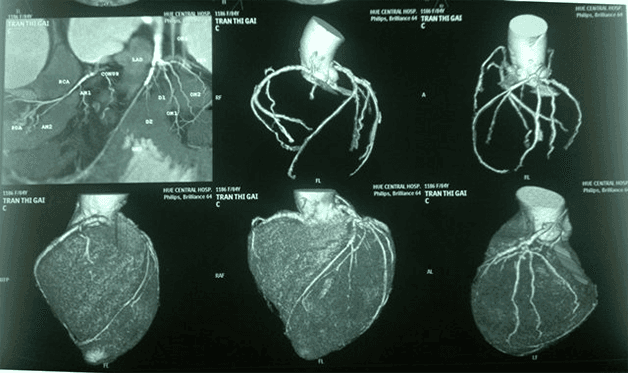

Trong những năm trở lại đây, chụp CT mạch vành (chụp cắt lớp vi tính) đã trở thành một chẩn đoán hình ảnh quen thuộc, quan trọng trong quá trình khám chữa bệnh mạch vành nói riêng và bệnh tim mạch nói chung. Trong đó, chụp CT dùng thuốc cản quang để đánh giá tình trạng hẹp động mạch và không cần thuốc cản quang giúp khảo sát mức độ vôi hóa mạch vành. Chụp CT mạch vành có những ưu điểm và một số lưu ý mà bạn nên biết.

Chụp CT cơ bản bao gồm 2 loại là chụp CT có tiêm thuốc cản quang để đánh giá tình trạng hẹp động mạch và chụp CT không tiêm thuốc cản quang để đánh giá tình trạng vôi hóa mạch vành:

3.2. Kỹ thuật chụp CT mạch vành tiêm thuốc cản quang

Kỹ thuật chụp CT có tiêm thuốc cản quang cho biết chắc chắn mức độ hẹp tắc, tình trạng hẹp động mạch vành, đạt khả năng loại trừ hẹp mạch vành đạt từ 97 – 100%. Đặc biệt, thuốc cản quang còn cho phép đánh giá tốt mức độ hẹp thành và lòng động mạch trên hình ảnh chụp CT. Những thông tin này có vai trò quan trọng trong việc chẩn đoán và điều trị bệnh.

Nhìn chung, đây là kĩ thuật đạt độ chính xác cao trong việc đánh giá bệnh mạch vành, cụ thể là đánh giá tái hẹp sau can thiệp điều trị trước đó hoặc hẹp mạch vành do xơ vữa động mạch. Tuy nhiên, do sử dụng chất cản quang nên kĩ thuật này không phù hợp với người bị dị ứng với thuốc cản quang, bệnh nhân suy thận hoặc mắc bệnh nặng khác.